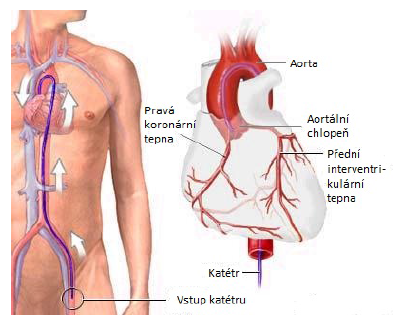

Většina výkonů se provádí endokardiálně (na obrázku 2.1 je uvedeno zavádění katétru), tj. katétry jsou do srdce vedeny cévním řečištěm, další možností je epikardiální či chirurgický přístup. Na začátku výkonu pokud není arytmie jednoznačně dokumentovaná a nebo není jasně známý mechanismus je nutné před vlastním výkonem provést elektrofyziologické vyšetření (EFV). Pomocí intrakardiálního EKG je arytmie zmapována a posléze je aplikována RF energie. Méně složité výkony jako je AVNRT, WPW syndrom, flutter síní I. typu jsou mapovány pouze s využitím intrakardiálního EKG a za RTG kontroly.

Obrázek 2.1: Způsob zavádění katétru – endokardiálně, převzato z [10]. |